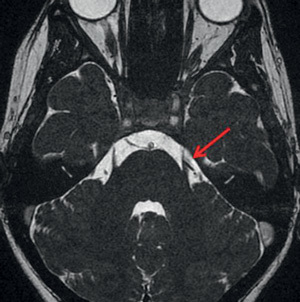

Quel est l’examen d’imagerie et la séquence? Quel diagnostic?

IRM séquence FLAIR infarctus cérebelleux gauche